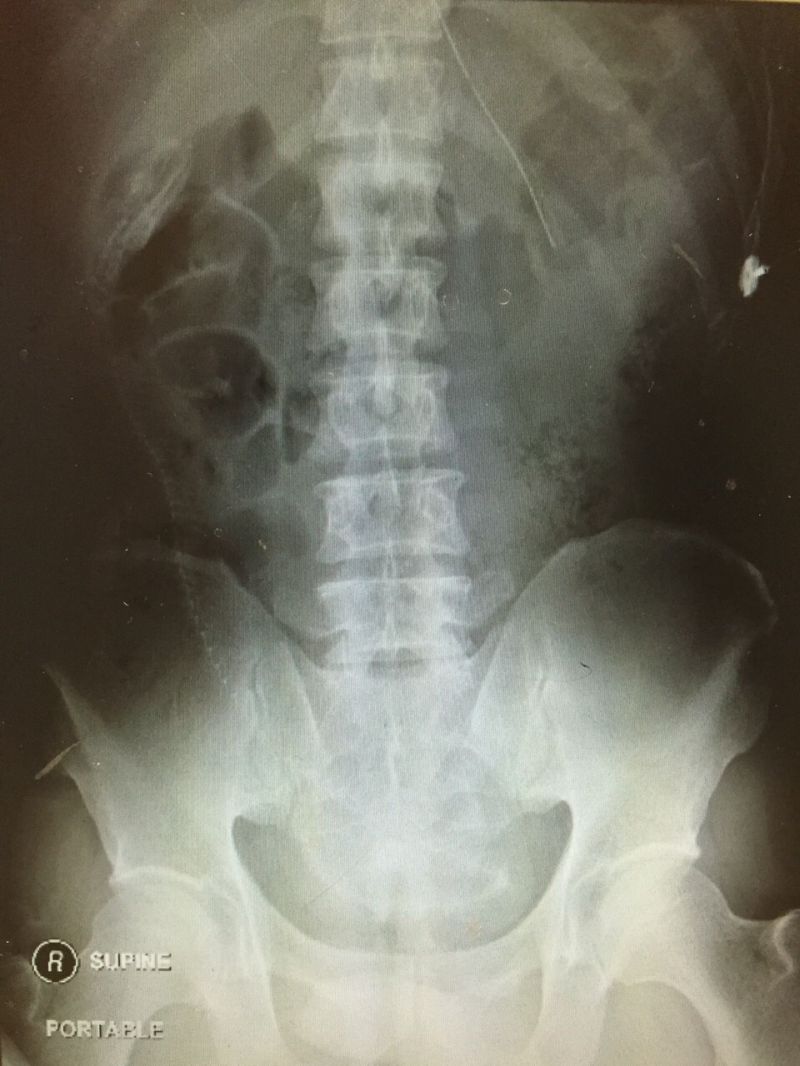

gif_animation ウナギでアナルオ●ニーしていた男の恐ろしい末路。男はお腹(腸内)に激しい痛みを訴え、病院を訪れた。それは手術により取り出され…。[4]images